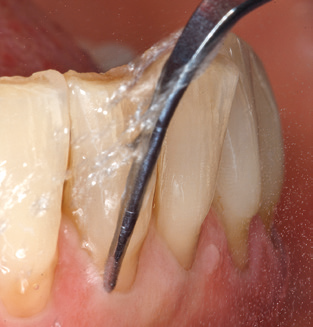

Fig. 4: Flexible probes with millimetre markings are recommended for the probing of dental implants (e.g. Colorvue Kit PCV11KIT6, Hu­Friedy). – Fig. 5a and b: A straight working tip (1P, W&H Dentalwerk Bürmoos GmbH) is a suitable instrument for use on all natural teeth. – Fig. 6: Curved working tips (3Pr/3Pl, W&H Dentalwerk Bürmoos GmbH) lend themselves to the processing of difficult-to-reach areas of the tooth and root surfaces (e.g. furcations). – Fig. 7: The tapered, hexagonal implant cleaning tip (1I, W&H Dentalwerk Bürmoos GmbH) permits atraumatic and efficient cleaning of the crown and abutment surfaces. – Fig. 8: Titanium and carbon curettes are suitable instruments for the manual cleaning of the implant surfaces.

Good illumination of the working field facilitates the process considerably. The system used by the authors achieves this thanks to a 5x LED ring integrated in the handpiece. Naturally, a range of working tips for different indications is also offered. A straight, universally employable tip is the basic instrument required for machine cleaning of natural teeth (Fig. 5a and b). Curved tips, which allow access to exposed furcations, are also available for hard-to-reach areas in the posterior region (Fig. 6).